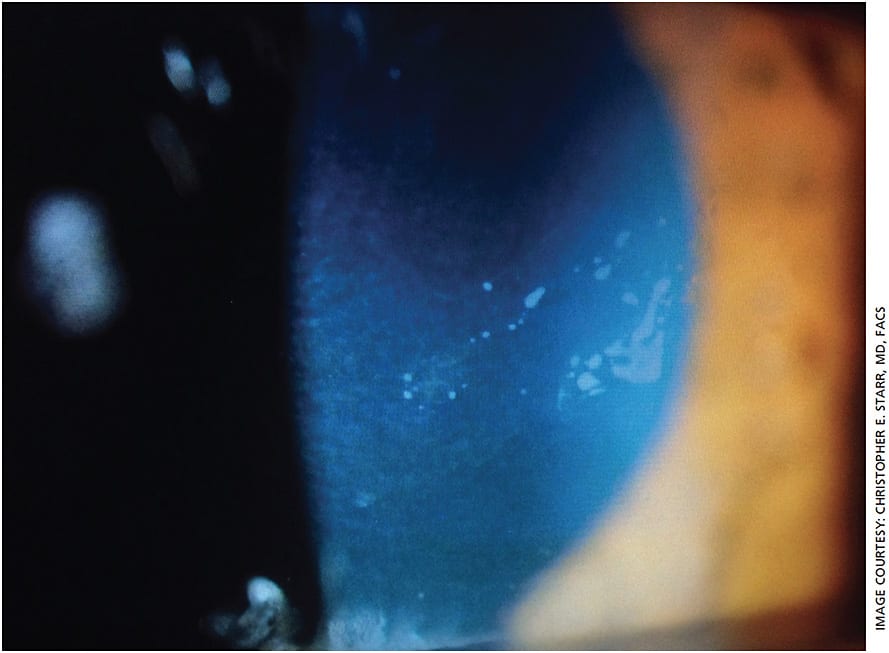

- Corneal and conjunctival staining. Performed with fluorescein and/or lissamine (green), this is a traditional and inexpensive test but also an effective and reliable way to assess the health of the ocular surface, including the quality of the tear film (Figure 1). Subtle corneal pathology, such as anterior basement membrane dystrophy (Figure 2), can also be identified with fluorescein, in addition to punctate staining of the cornea and conjunctiva.

Figure 2. Slit lamp exam reveals anterior basement membrane dystrophy, which can present with patient complaints of dry eyes, grittiness and other similar symptoms. - TBUT. Also traditionally performed with the slit lamp, TBUT tests are extremely important, particularly in evaporative DED, which is the most common subtype and usually results from either a lack of lipid or meibum, or poor quality meibum, in the tear film. While most clinicians still use the slit lamp, many are also turning to complementary devices like Visiometrics’ HD Analyzer or the Oculus Keratograph 5M, which do not require dye and can be operated by ophthalmic technicians. “[TBUT] is very objective and reproducible. In fact, when you look at the 2017 Tear Film and Ocular Surface Society DEWS II report diagnostic algorithm, non-invasive tear breakup time was the recommended first-line test. The tear osmolarity test and the non-invasive tear breakup time, in addition to corneal staining, were the key diagnostic steps in their algorithm,” says Dr. Starr.